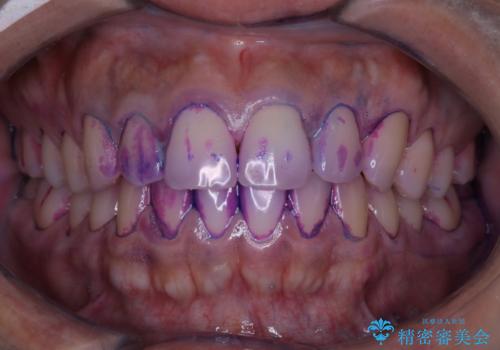

実はこんなに磨き残しが!!!

- 半年ぶりにクリーニングを希望とのことでした。

染め出しをしての磨き残しチェックとPMTC60分コースを行いました。

しかし、プラークは歯の色と似ているため、見ただけでは付着しているかどうかがハッキリとは分かりません。

染め出し液を使ってプラークを染め出すことにより、普段の歯みがきで磨き残している場所を目で確かめることができます。

日々の歯磨きを上達するには、まずどこが磨けていないか認識することが大切です。